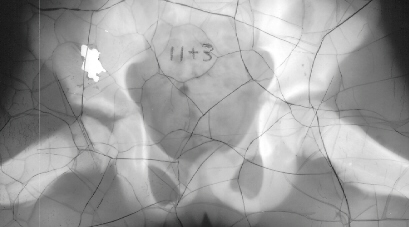

12 years of age. At 16 years of age, 10 degrees limitation of internal

rotation as compared to the opposite side was still observed but the patient

was asymptomatic. X-ray 4 was taken at 17 years of age.